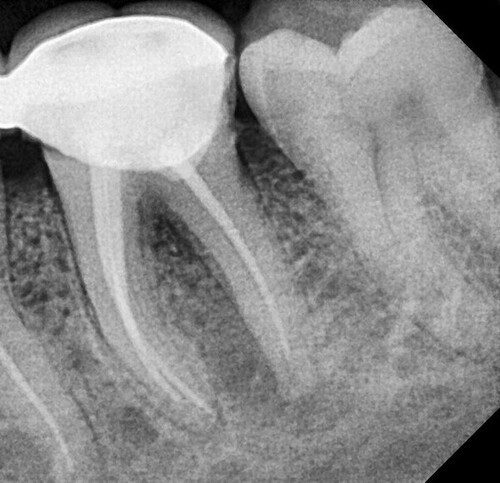

Клинический осмотр выявил наличие десневой ткани через отверстие доступа на нижнечелюстном левом первом моляре, что произошло в частной клинике (рис. 1). При рентгенографическом обследовании на левом первом моляре нижней челюсти была обнаружена перфорация на дистолингвальной стороне дна пульпы. На соседнем премоляре также присутствовал проксимальный кариес (Рисунок 2).

Рис. 2